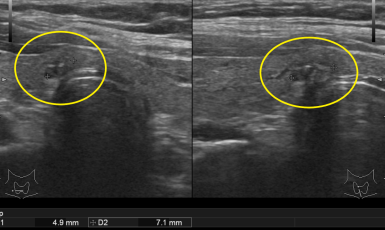

303번째 갑상선암 진단사례 (2019년5월23일) 목 앞쪽에 단단한 혹이 만져지고 불편감이 있어 진료위해 내원해 주신 환자분이셨습니다. 진찰상 앞쪽 목, 즉 오른쪽 갑상선..